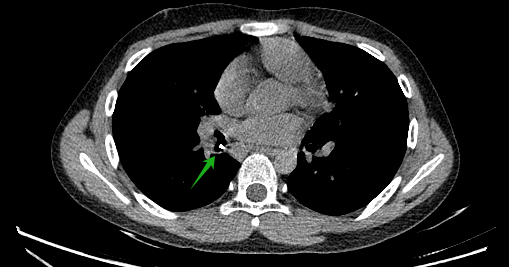

案例三

小熙,男,1岁,家人喂食黄鳝饭时出现呛咳,随后开始出现喘息症状,遂收入院。入院查体双侧呼吸音不对称,左侧呼吸音减低伴喘鸣,完善胸部CT检查,发现左主支气管管腔内见一高密度影,考虑左主支气管异物伴左肺阻塞性肺气肿,遂行“支气管镜气管异物取出术+肺泡灌洗术”,取出一骨性异物,术后咳嗽喘息症状缓解。

(箭头高密度为异物)

(箭头为左主异物)